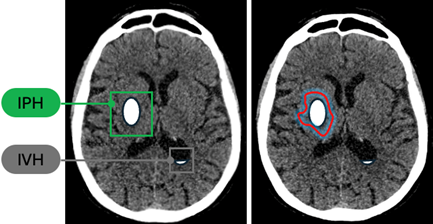

L’analyse des discordances a montré des profils d’erreurs similaires entre les deux cohortes et les études précédentes. Les faux négatifs concernaient principalement des lésions de petite taille (< 10 mm), des hémorragies isodenses ou des localisations proches de la base du crâne (voir image 3). Les faux positifs étaient liés à des tumeurs intra-axiales, des calcifications, des artefacts ou des structures anatomiques normales telles que la faux du cerveau, la tente du cervelet ou les sinus veineux (voir image 4).

Image4 clotide ruesh.png

Image 4 : Exemples de faux positifs pour les deux cohortes.